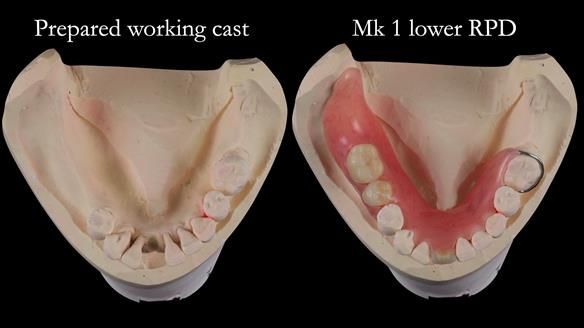

Welcome to my Newsletter 54 showing the making and fitting of dentures (a complete upper metal reinforced denture, a lower immediate partial denture and a definitive Scandinavian designed, metal based lower partial denture) for David, a 75 -year-old man. The full protocol workflow is presented including the use of dentate photographs to mimic his natural teeth.

The clinical situation and treatment process is shown in detail below. I provided the clinical work. Rowan Garstang, my dental technician, provided the technical work.

Interestingly we found that the upper complete denture when finished and fitted didn’t have good enough retention for David’s satisfaction. It was relined by adding compound to the buccal flanges – to almost overextend into the sulcus to ‘create’ a sulcus, followed by using a light bodied silicone impression material. This improved the function of the C/-considerably. A lower Scandinavian hygienically designed lower RPD was also provided which helped with occlusal stability and reseating the upper denture – further improving the fit.